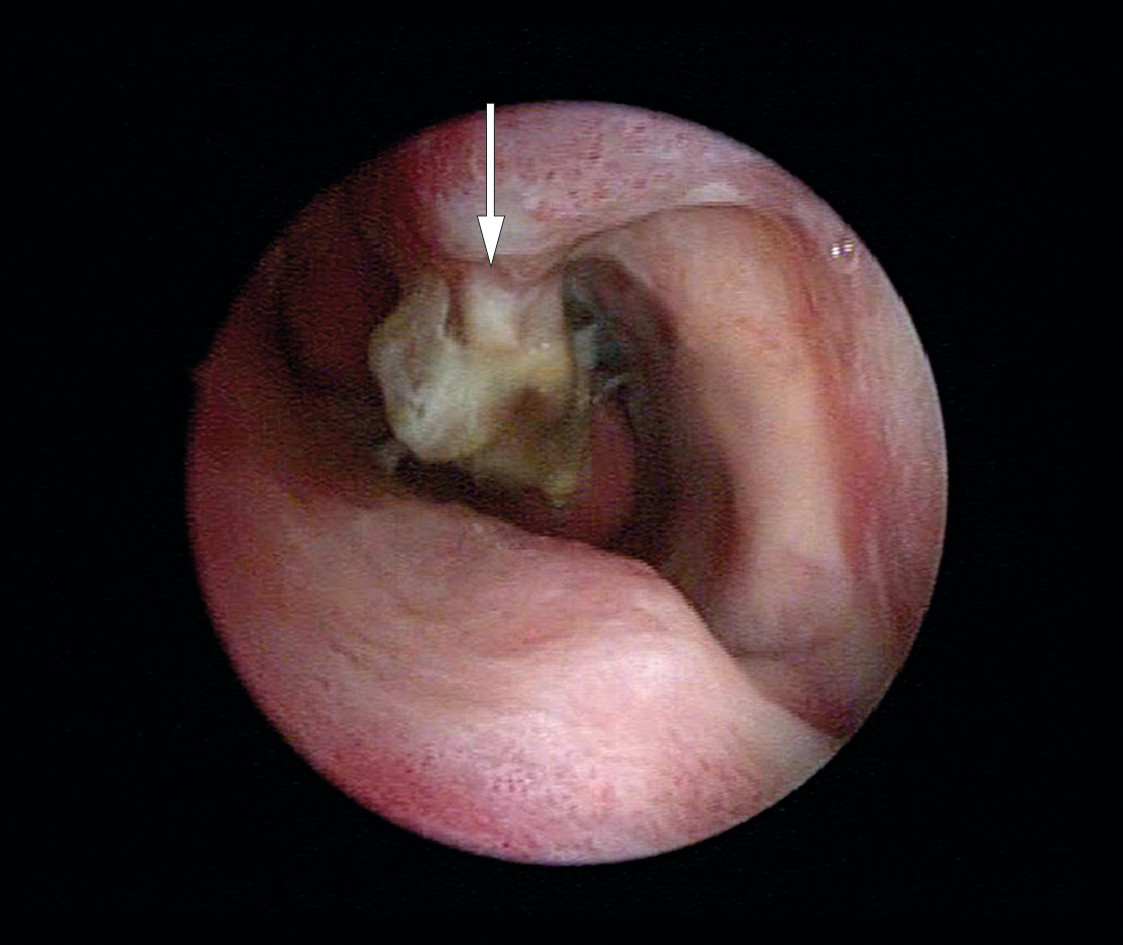

19 dager etter operasjonen tok hun kontakt med øre-nese-halsavdelingen og klagde over dårlig lukt i nesen. Nasal endoskopi viste store mengder skorper, og concha nasalis inferior hadde nekrose og tap av bensubstans. Man mistenkte kronisk osteomyelitt med lokal bakteriell spredning på grunn av infeksjon etter kirurgi (1, 2).

Patologen beskrev tilstanden som «kronisk inflammasjon og nekrose forenelig med osteomyelitt» (figur 1). Bakteriologisk dyrkning viste vekst av Streptococcus pneumoniae, Moraxella catarrhalis og blandet anaerob flora. Bakteriene var sensitive for erytromycin og metronidazol, og kloksacillinbehandlingen ble erstattet med en ti dagers kur med erytromycin og metronidazol peroralt.